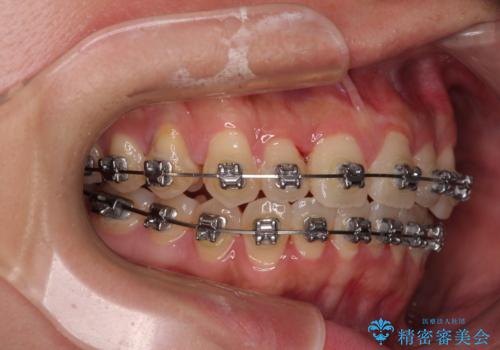

- メタルブラケット

- 治療期間

- 1年4ヶ月

歯列矯正では基本的に骨格を改善することはできませんが、急速拡大装置(MARPE)を使用することで上顎骨を側方に拡大させることができ、咬合状態を大きく改善することができます。